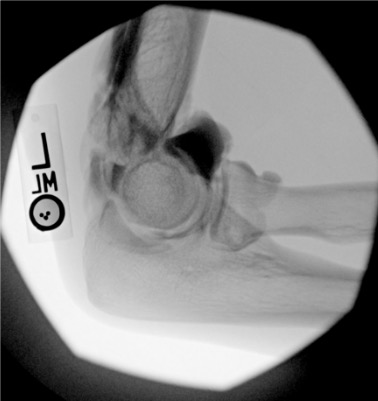

| Elbow | 3–5 mL | Fluoroscopy or ultrasound | Lateral (radiohumeral) approach | Triangle formed by lateral epicondyle, radial head, and capitellum; elbow flexed 90°; posterior fat pad elevation on lateral radiograph suggests intra-articular effusion and facilitates access |

Elbow

Needle placementPost-injection